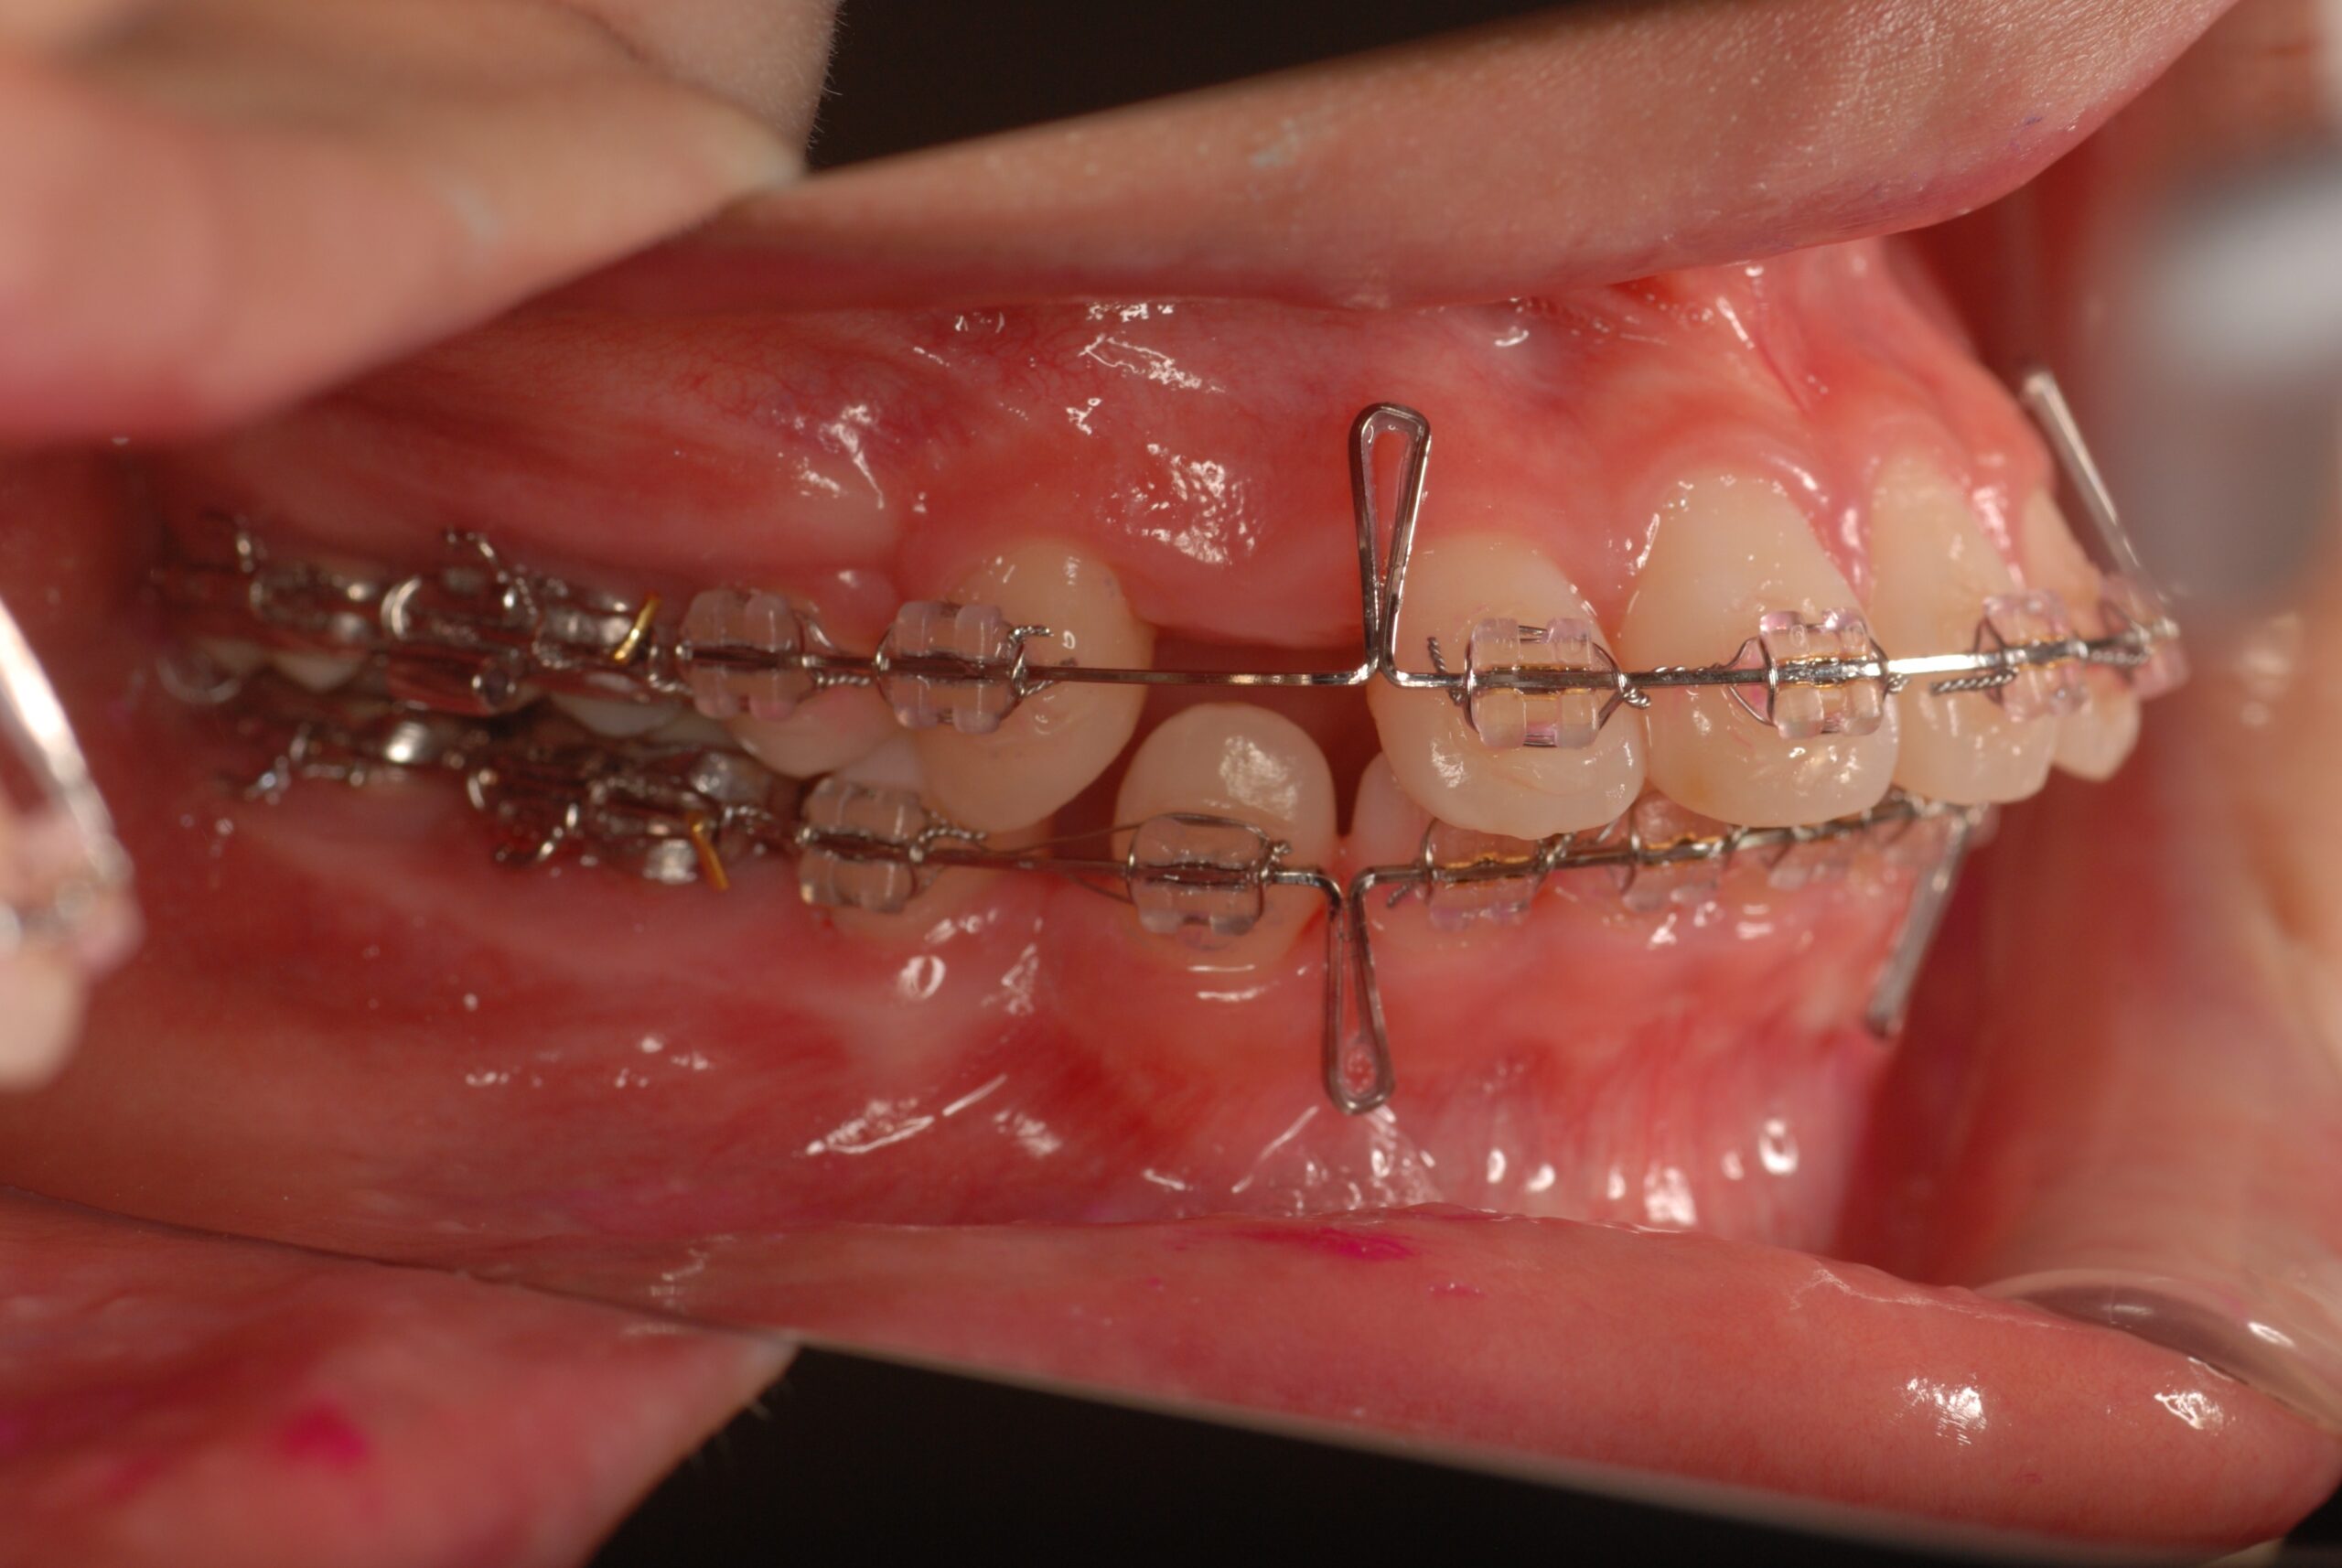

Progress

- 上顎前突、叢生。 上下顎第一小臼歯を抜歯し、抜歯空隙を利用し、顎外固定装置としてヘッドギヤを併用しながら、上顎前歯を可及的に後退させる。